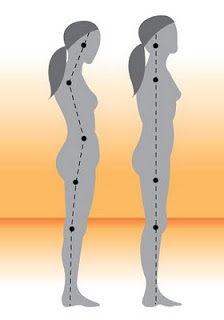

Postura errada provoca barriga e dores nas costas

Sentar e andar com a postura correta não é apenas esteticamente mais bonito, como também pode evitar dores e lesões na coluna. Para quem se preocupa com a boa forma, vale ainda lembrar que a postura pode gerar barriga. É o que explica o fisioterapeuta e presidente da Sociedade Brasileira de RPG, Oldack Barros. "A má postura cria uma pequena barriga abaixo do umbigo, pois provoca a perda do tônus muscular na região", disse ele.

Segundo Barros, o abdômen é um músculo que precisa de contração e fortalecimento. Quando uma pessoa está com uma postura ereta, obriga a contração da barriga, explicou o profissional. Ele alertou ainda as mulheres que andam muito empinadas, jogam o bumbum para trás e, consequentemente, o abdômen para frente, tendem a ter uma barriga inteiriça causada pela má postura. Já aquelas que projetam o quadril e pescoço para frente, mas encolhem o bumbum, podem desenvolver a barriga abaixo do umbigo.